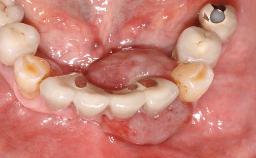

A male patient had lost teeth 11 and 22 as a result of a bicycle accident at age 14. In his adolescent years, a removable prosthesis had replaced the missing teeth. At age 21, the patient was referred by his dentist to the university clinic for treatment of the missing teeth 11 and 22 with implants. He was in good health and a nonsmoker. The absence of teeth 11 and 22 over many years had led to significant atrophy of the alveolar ridge, particularly at site 11. As a first step, the alveolar ridge was augmented using a block graft to replace the lost bone. A Straumann SP implant (diameter 4.1 mm, length 12 mm; Institut Straumann AG, Basel, Switzerland) and a Straumann Narrow Neck implant (length 10 mm) were inserted in the correct location and axial position at sites 11 and 22, respectively, six months later. After three months of healing and subsequent reentry, the patient returned to the referring dentist to receive the prosthetic restoration. The patient was seen again six months after the restoration had been placed. The frontal view showed a high smile line, an irregular gingival profile, and a bluish-gray tinge to implant crowns 11 and 22 compared to the natural dentition.